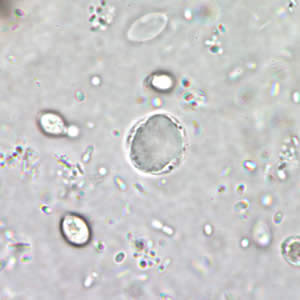

Blastocyctis hominis